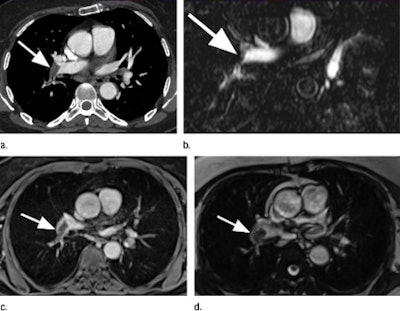

| Pulmonary embolus (arrow) of the right pulmonary artery in a 67-year-old woman. The images include a CT pulmonary angiogram (a), axial reformation of bolus-triggered 3D MR pulmonary angiogram (b), 3D gradient-echo MR image (c), and a triggered true FISP MR image (d). Images courtesy of Radiology. |

CT angiography detected a total of 67 pulmonary emboli, while 56 emboli were detected through the overall MRI exams. The 3D gradient-echo MRI sequence had the highest accuracy, at 90% in diagnosis, while the 3D MR pulmonary angiography sequence showed the lowest sensitivity, at 55%.

In the follow-up analysis, MR pulmonary angiography achieved sensitivity of 55% for pulmonary embolism detection, compared with 67% sensitivity for triggered true FISP and 73% sensitivity for gradient-echo MRI. The combination of all three MR sequences improved overall sensitivity to 84%.